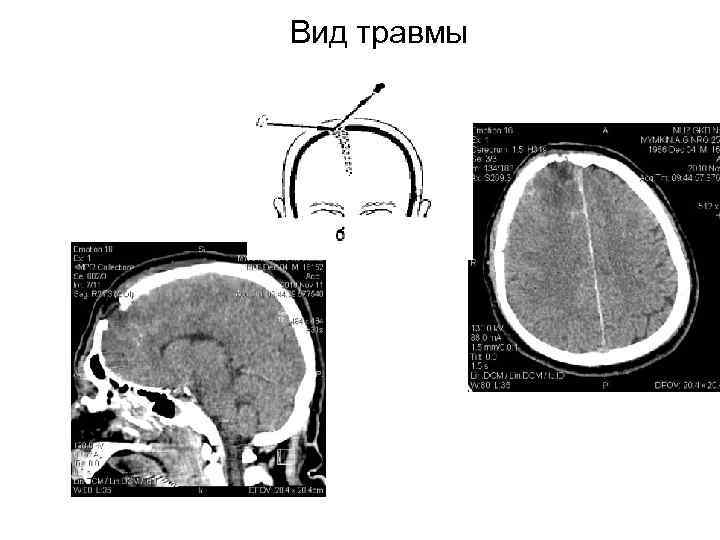

Вид травмы